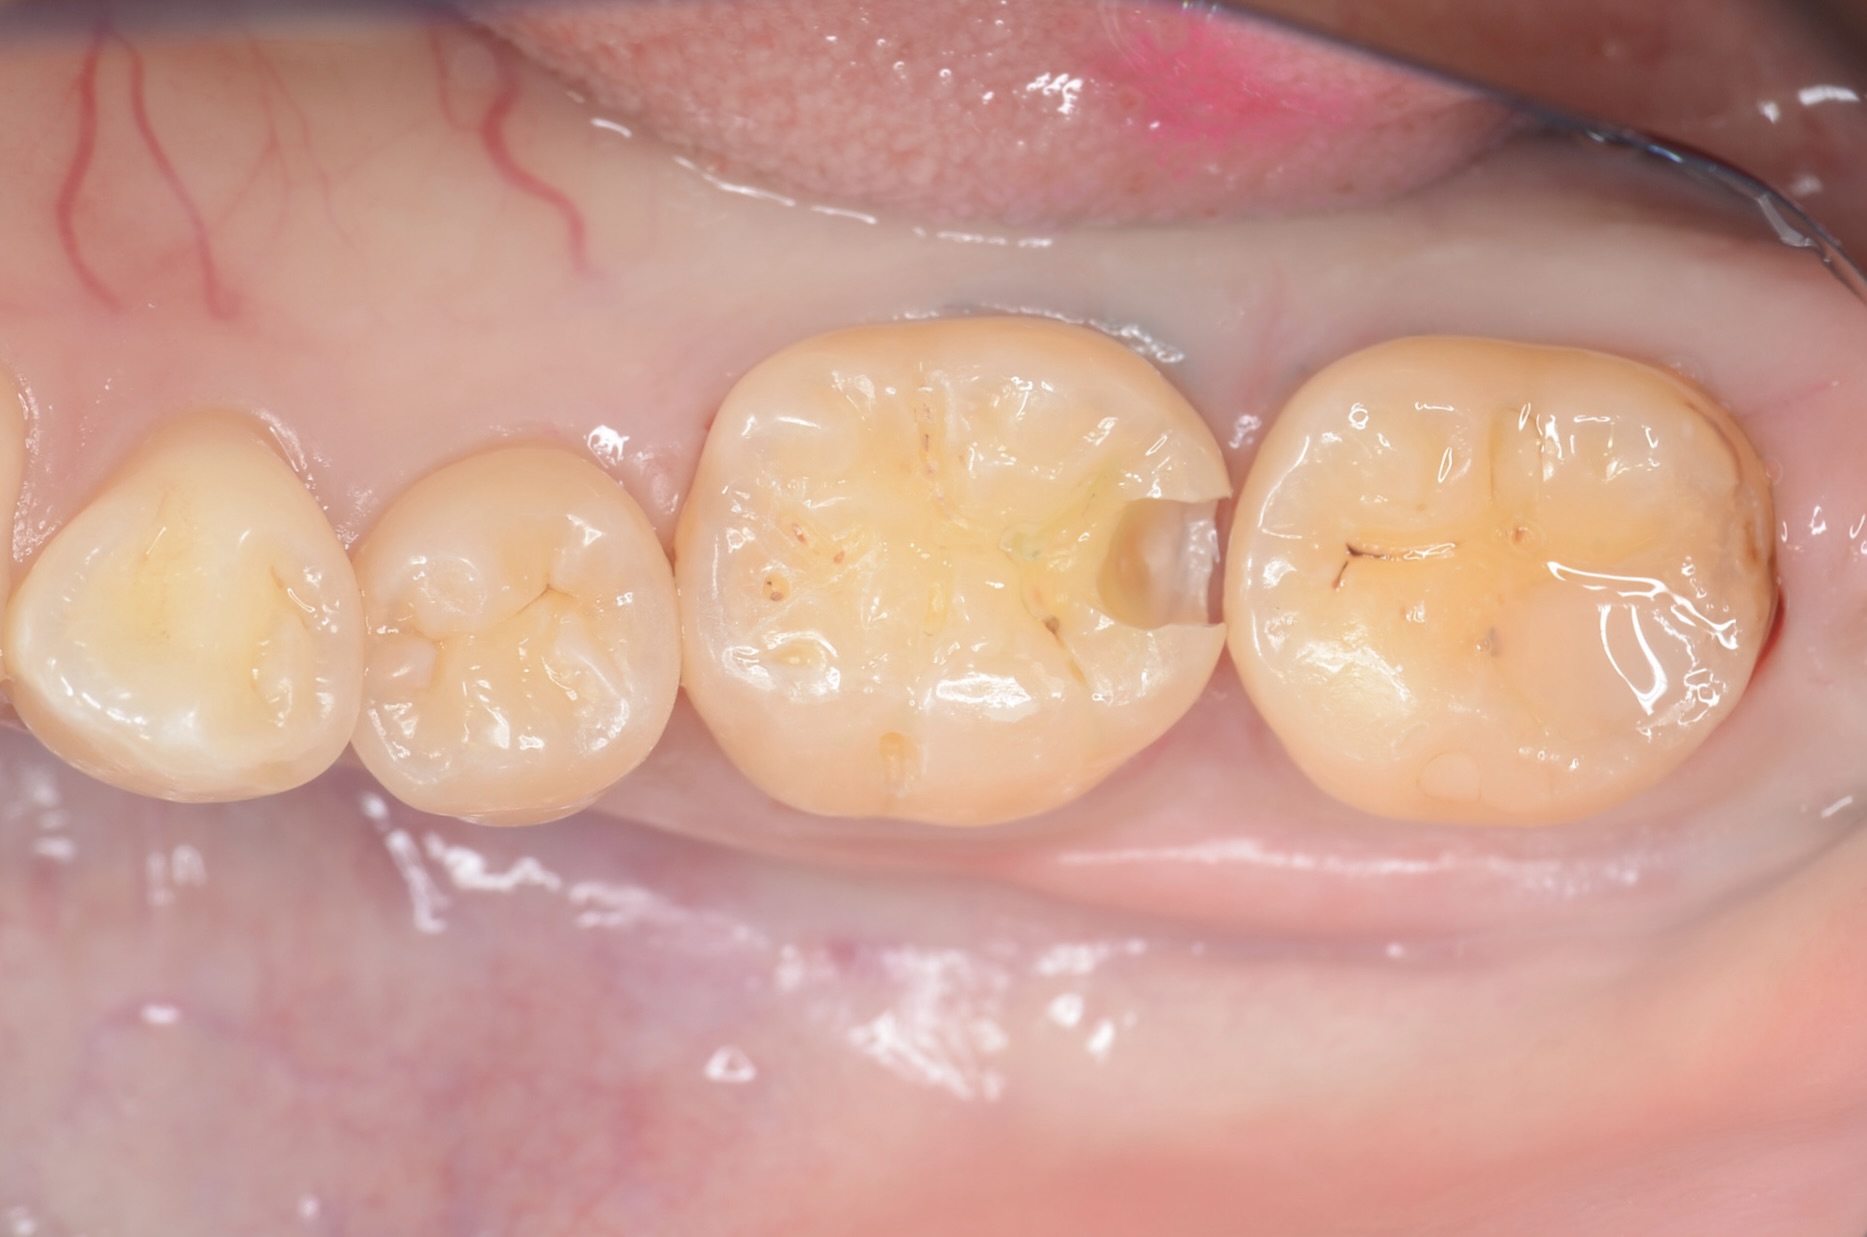

6番の遠心隣接面が黒くなっています。 虫歯があります。痛みはなかったようです。 -

エナメル質がうっすら灰色になっている部分から、少し歯を削ってみると中が虫歯になっていました。 -

7番近心面の虫歯

7番近心に虫歯があります。 齲蝕検知液で青く染まります。 -